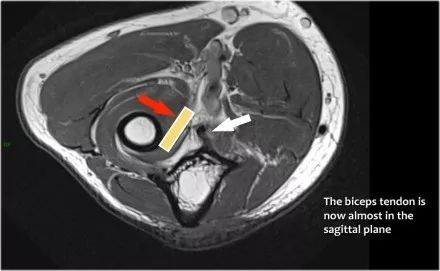

下面是另一种情况。在矢状图像上,我们不确定可能的撕裂。也许只有一些肌腱炎或肌腱炎。轴向图像显示部分撕裂(红色箭头)。

始终确保你的轴向扫描一直到结节,因为你太早停止,就像在这种情况下,你只会看到增厚的肌腱和一些液体,但你不确定可能的撕裂。